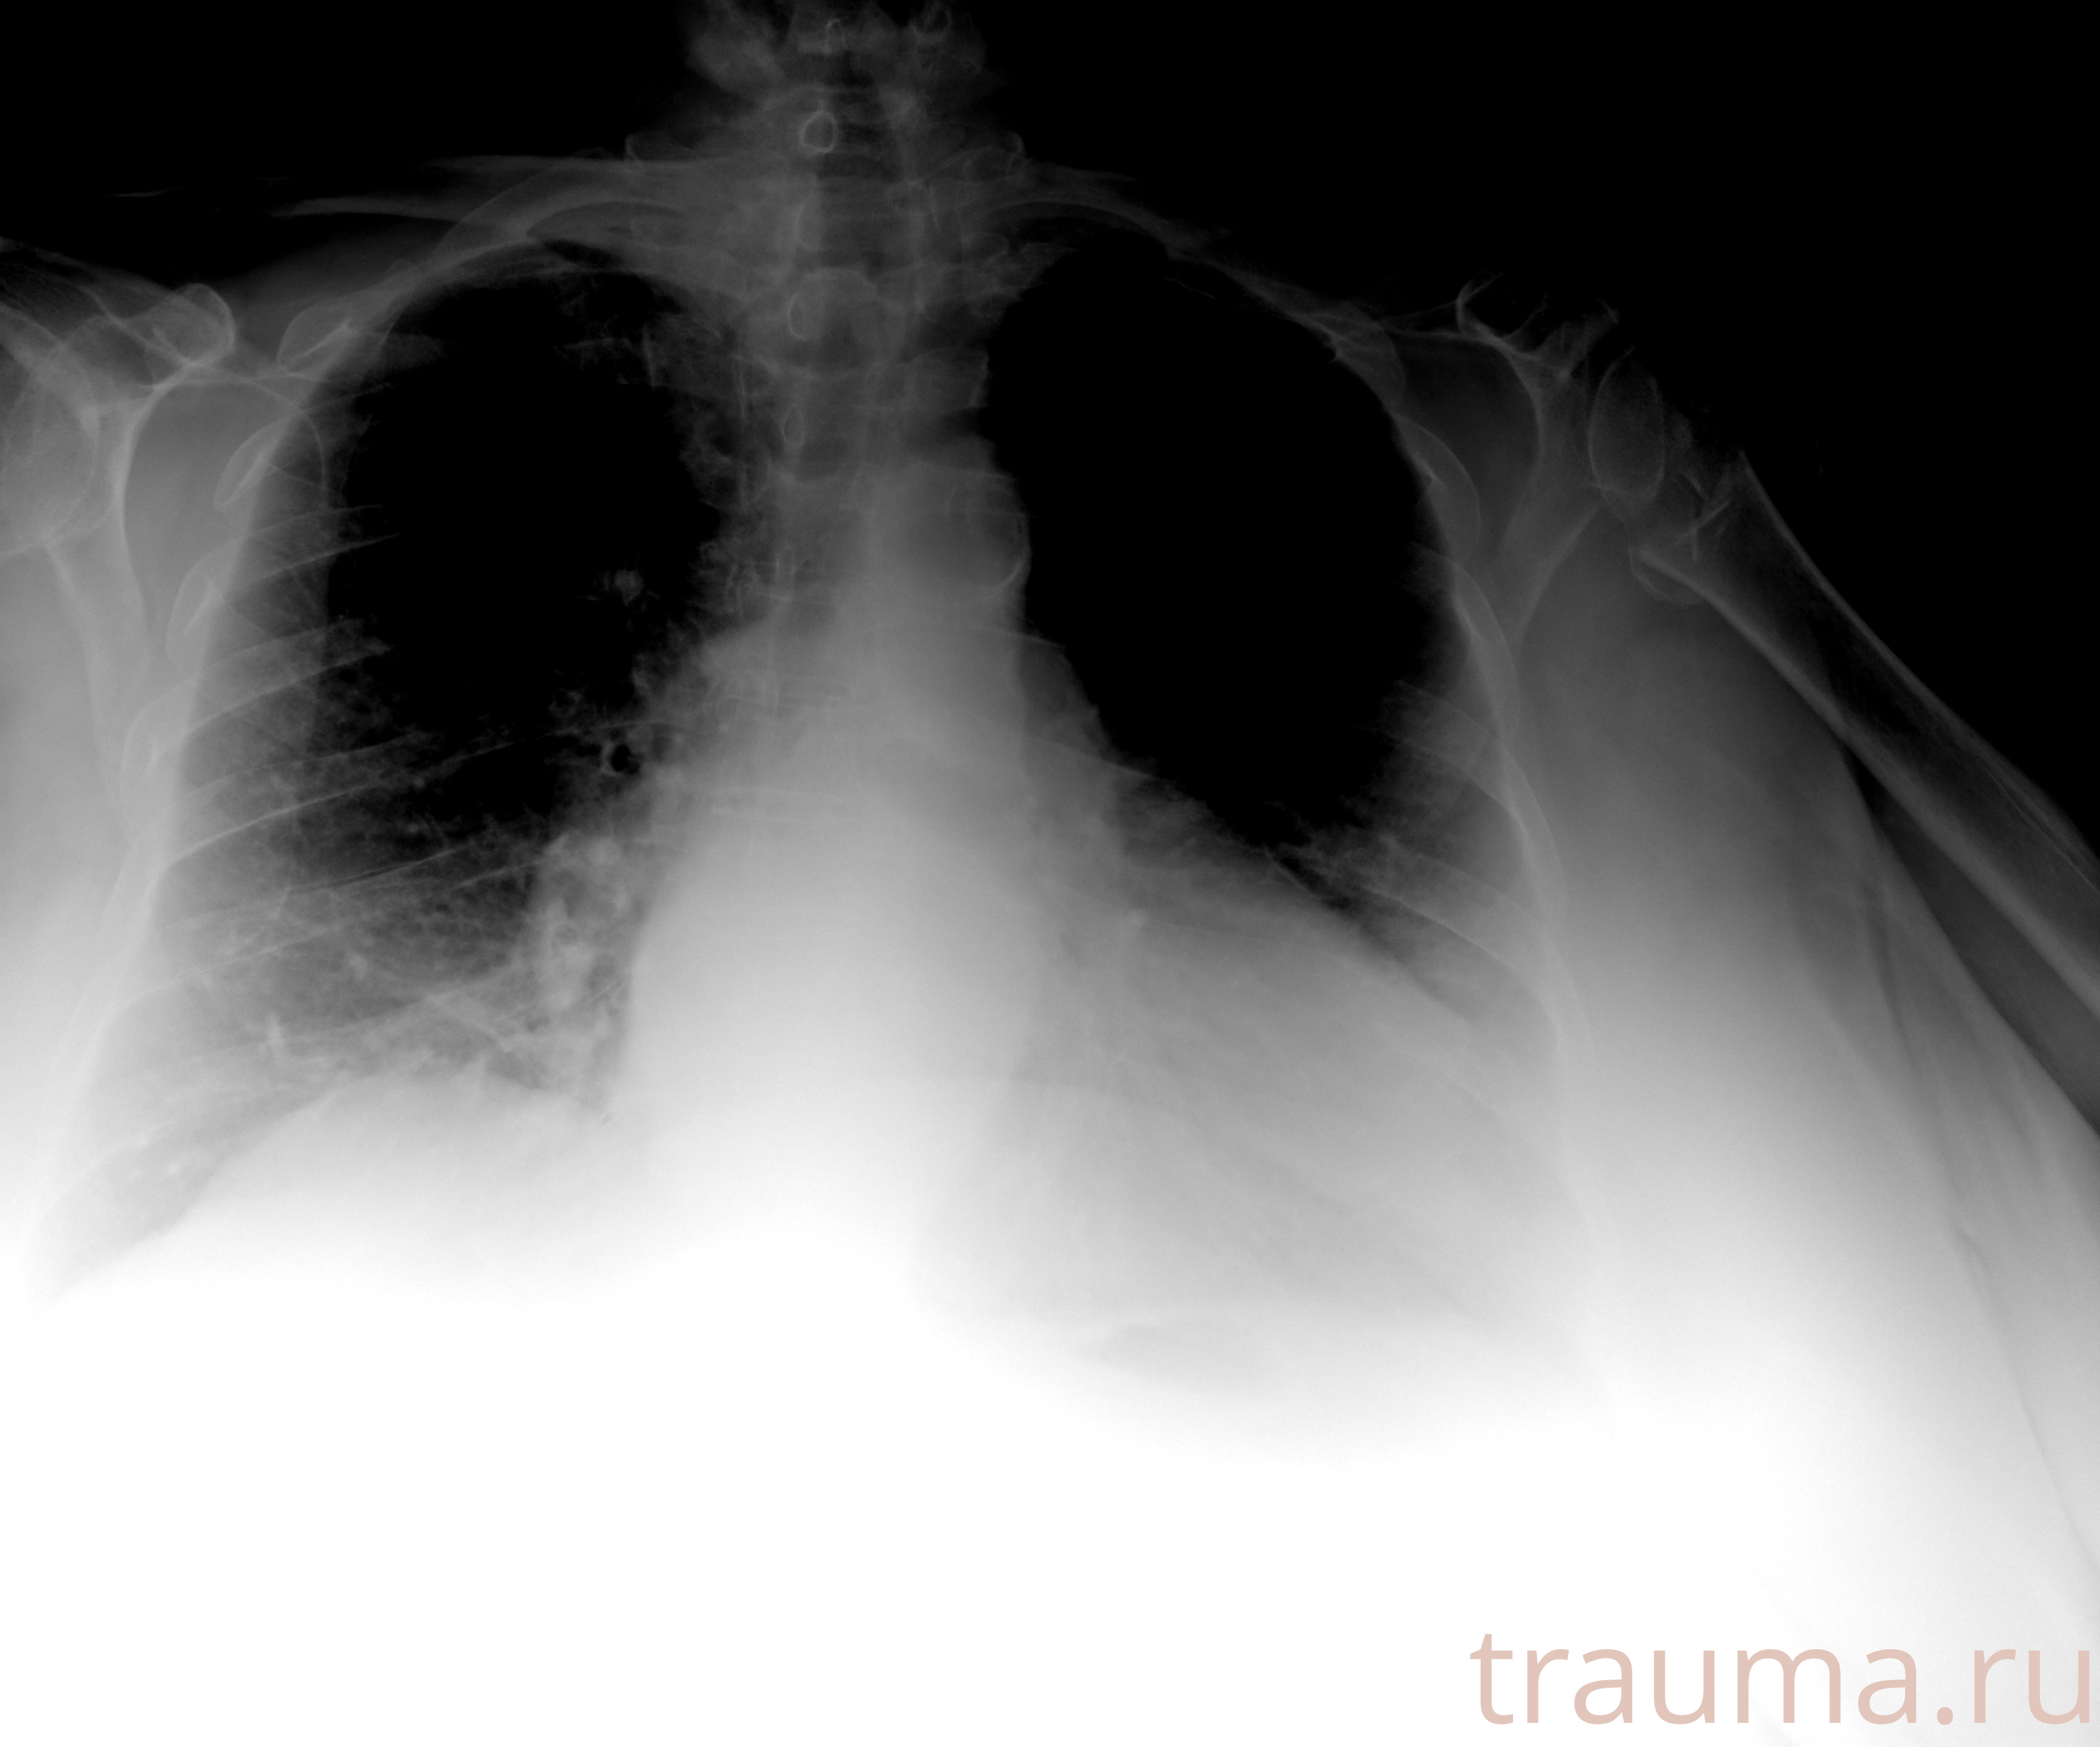

Рентген на дому: по вашему адресу приезжает врач-рентгенолог, травматолог-ортопед с мобильным рентгеновским аппаратом, проводит диагностику травмы или заболевания, делает необходимые рентгенограммы, дает рекомендации по дальнейшему лечению. Получить качественные снимки в домашних условиях возможно благодаря уникальной методике, разработанной МосРентген Центром для института  Склифосовского

при переломе шейки бедра и пневмонии от компании МосРентген Центр - партнера Института имени Склифосовского